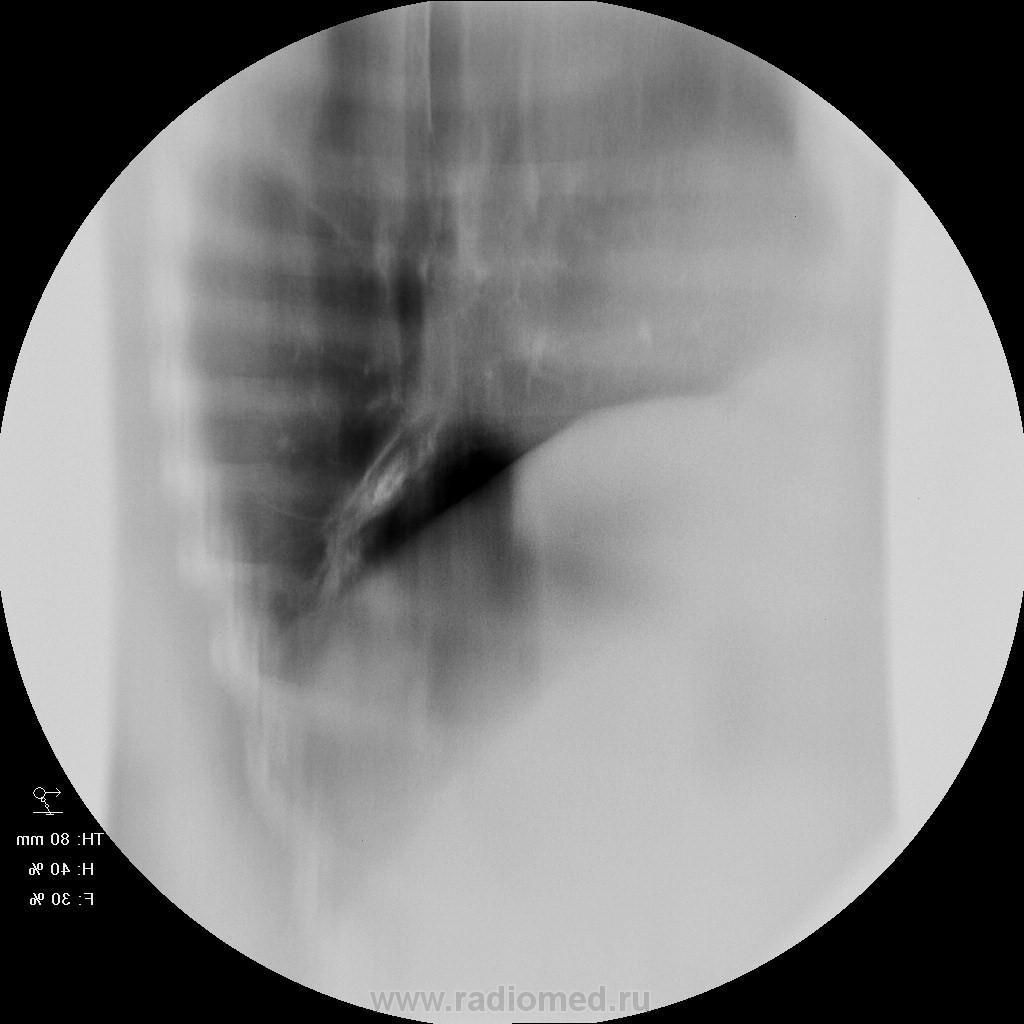

Женщина 50 лет поступила а пульмонологическо отделение с клиникой и диагнозом обострения бронхита. 15 лет назад перенесла тяжелую пневмонию нижней доли правого легкого. после этого находили выше указанные изменения в легих и наблюдали у фтизиатров. со слов " дисковидная туберкулема" или что-то вроде этого. на флю - картина на протяжении всего времени стабильная. на фбс - нижнедолевой бронх для эндоскопа не проходим, контактная кровоточивость, взята биопсия. прошу совета. какие будут мнения? выставляю только томо - снимки обычные не снимал. но картина на них подобная. по анализам без особенностей. не худела...

так как обозвать эту линзу с плотностью кальцинта? я вижу ателектаз-гиповентиляцию нижней доли, на фоне чего - эта "линза" - постпнемонический фиброателектаз?

А это не может оказаться обычным бронхолитиазом?

а причина этого "камня"? мог ли он образоваться после даже тяжелой пневмонии? что еще так может выглядеть? но главное для меня - добро или зло? я склоняюсь к какому то доброкачественному процессу, конечно, основываясь на стабильности картины на потяжении очень долгого времени...

Обычно бронхолитиаз возникает в результате пролежня кальцинированного лимфоузла в корне легкого.

Мне очень импонирует мысль о БРОНХОЛИТИАЗЕ....